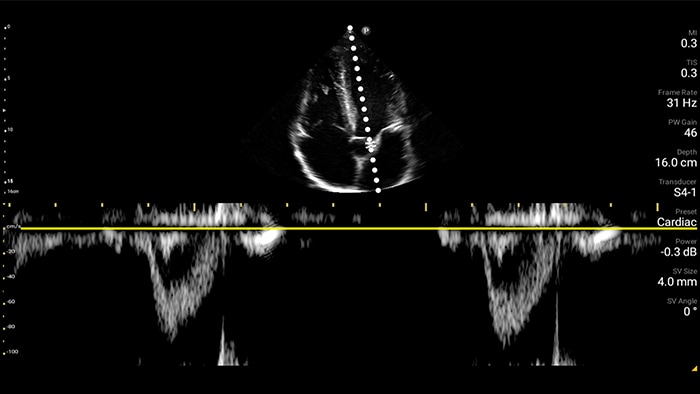

Beoordeling van de functie van het linkerventrikel

Congestief hartfalen is een groeiend probleem. Door echografie op uw praktijk te bieden, kan deze aandoening vroegtijdig worden ontdekt en de overlevingskansen aanzienlijk worden verbeterd.

Harttamponade vermomt zich als buikpijn